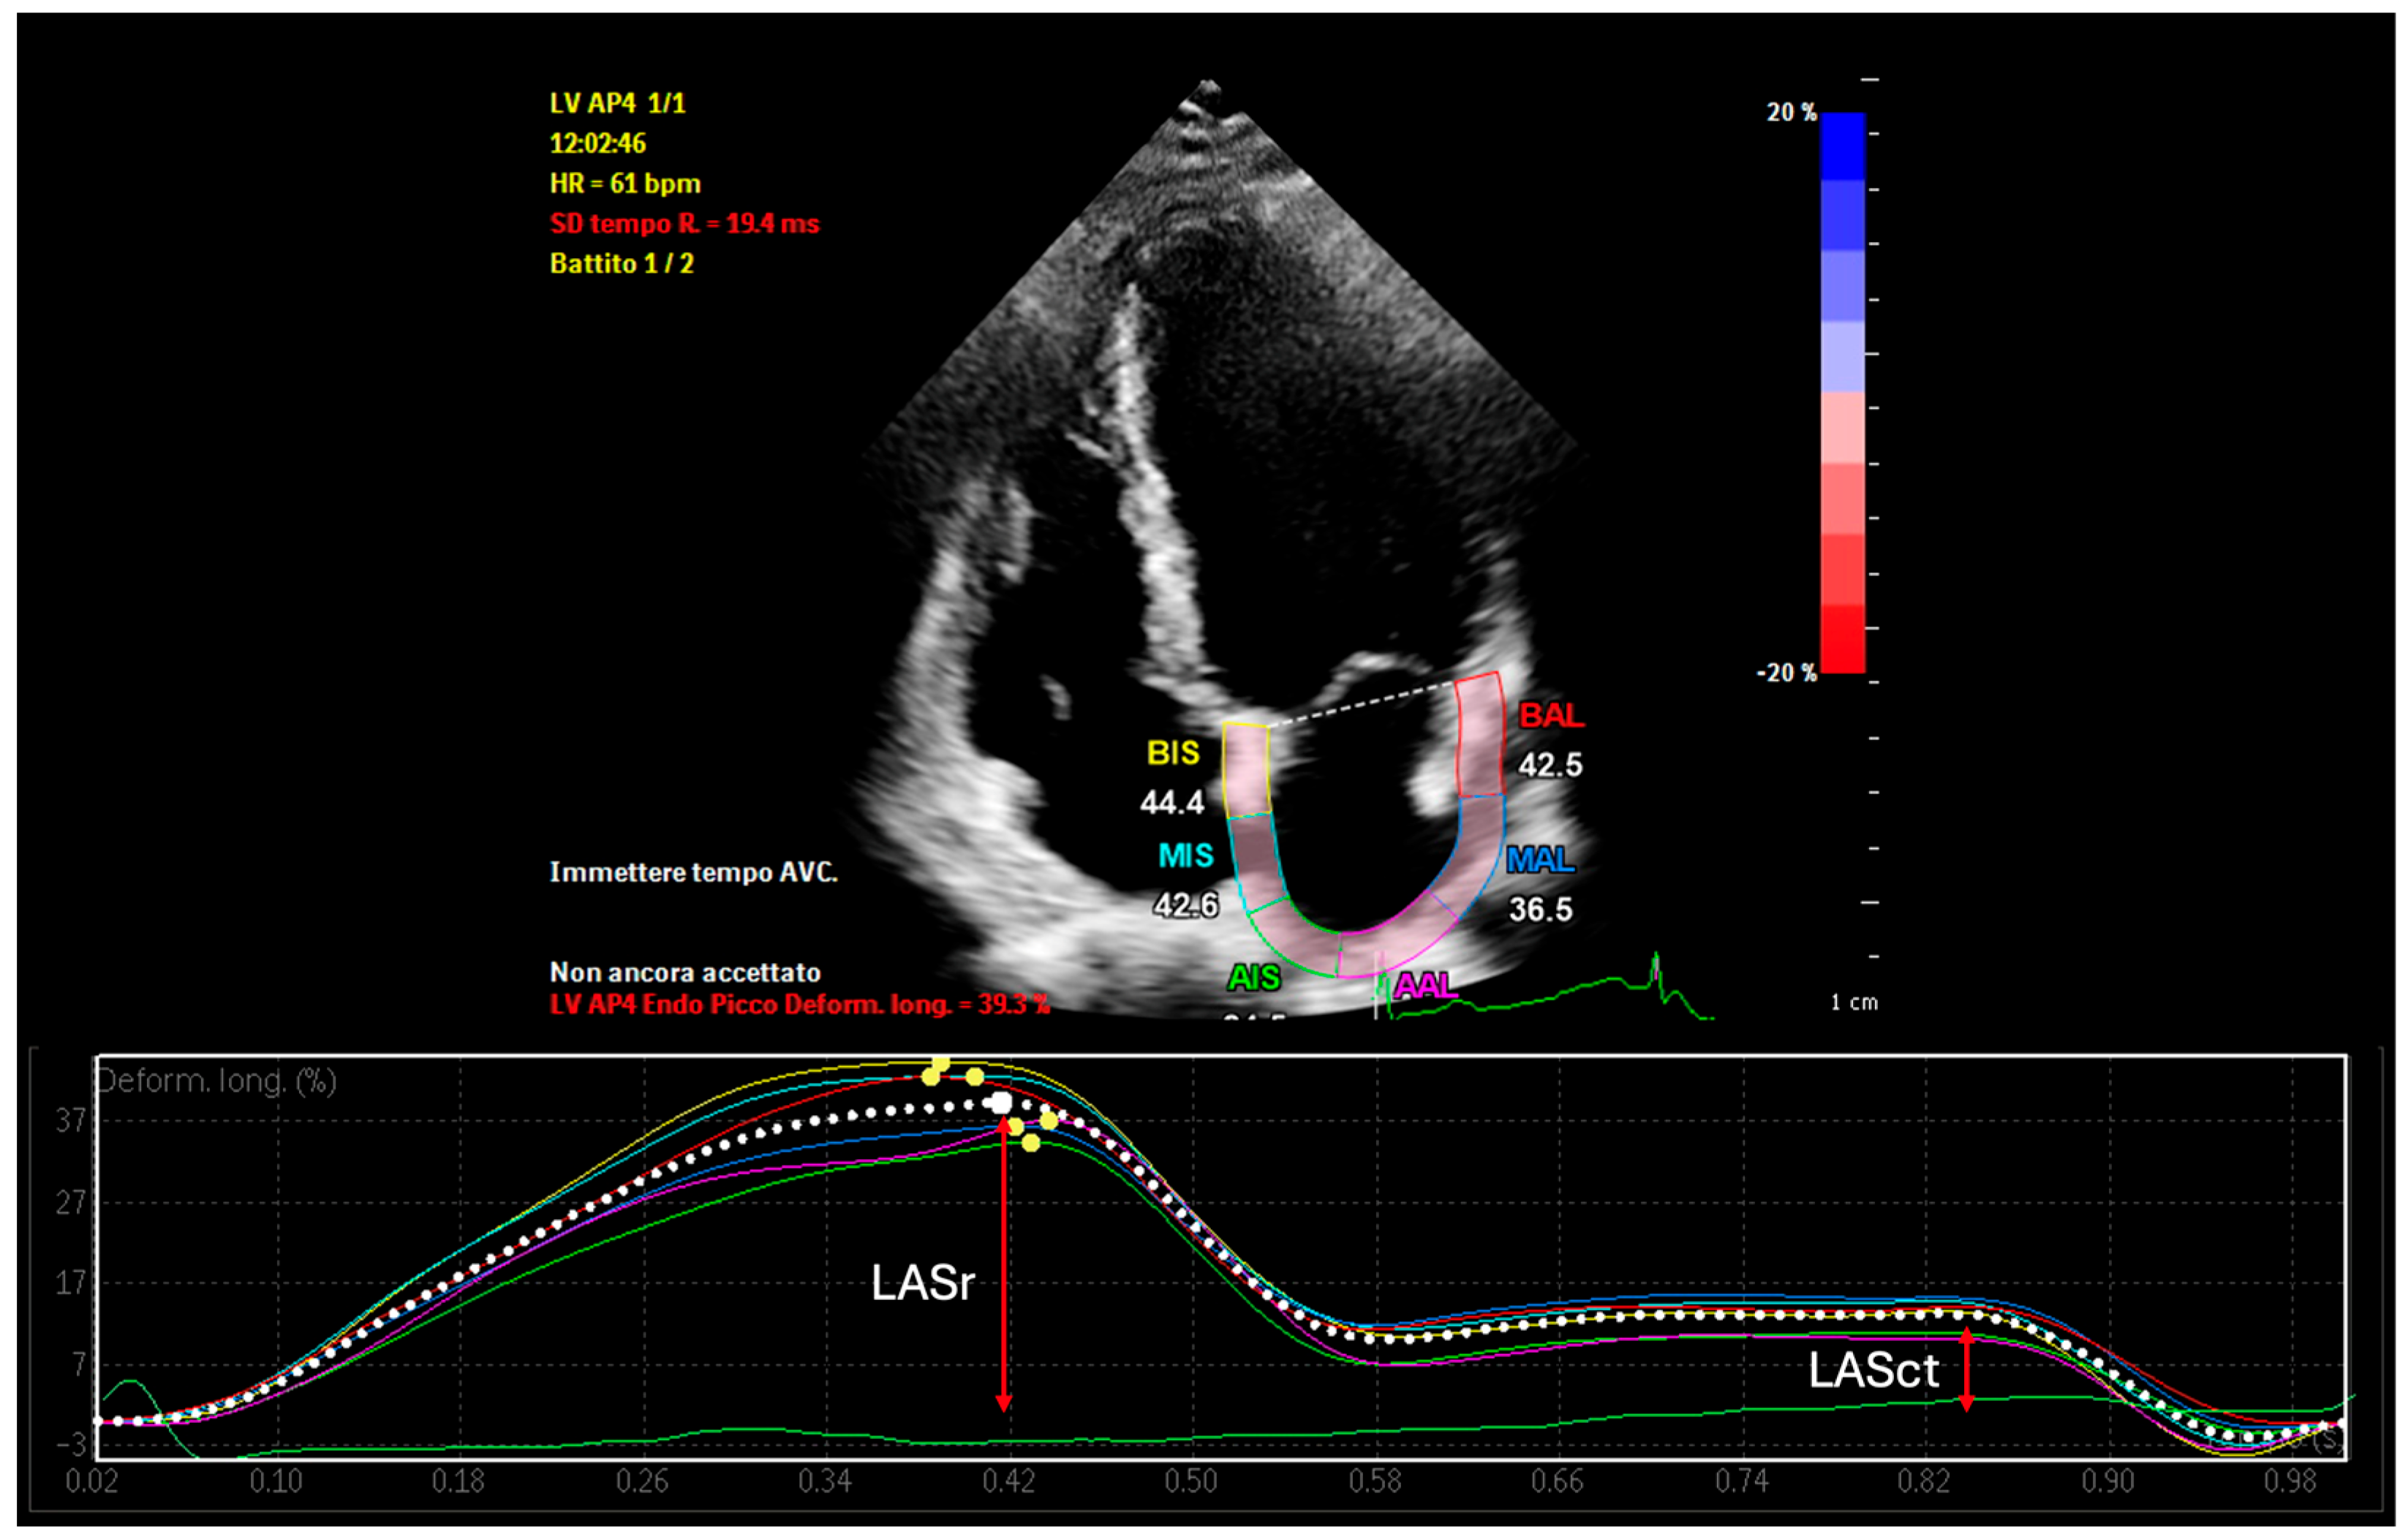

| LASr | Left Atrial Reservoir Strain |

| LASct | Left Atrial Contractile Strain |

- Hoit, B.D. Left Atrial Reservoir Strain: Its Time Has Come. JACC Cardiovasc. Imaging 2022, 15, 392–394. [Google Scholar] [CrossRef]

- Pathan, F.; D’ELia, N.; Nolan, M.T.; Marwick, T.H.; Negishi, K. Normal Ranges of Left Atrial Strain by Speckle-Tracking Echocardiography: A Systematic Review and Meta-Analysis. J. Am. Soc. Echocardiogr. 2017, 30, 59–70.e8. [Google Scholar] [CrossRef]

- Mirza, M.; Caracciolo, G.; Khan, U.; Mori, N.; Saha, S.K.; Srivathsan, K.; Altemose, G.; Scott, L.; Sengupta, P.; Jahangir, A. Left atrial reservoir function predicts atrial fibrillation recurrence after catheter ablation: A two-dimensional speckle strain study. J. Interv. Card. Electrophysiol. 2011, 31, 197–206. [Google Scholar] [CrossRef]

- Nielsen, A.B.; Skaarup, K.G.; Djernæs, K.; Hauser, R.; San José Estépar, R.; Sørensen, S.K.; Ruwald, M.H.; Hansen, M.L.; Worck, R.H.; Johannessen, A.; et al. Left atrial contractile strain predicts recurrence of atrial tachyarrhythmia after catheter ablation. Int. J. Cardiol. 2022, 358, 51–57. [Google Scholar] [CrossRef] [PubMed]

- Kiliszek, M.; Uziębło-Życzkowska, B.; Krzyżanowski, K.; Jurek, A.; Wierzbowski, R.; Smalc-Stasiak, M.; Krzesiński, P. Value of Left Atrial Strain in Predicting Recurrence after Atrial Fibrillation Ablation. J. Clin. Med. 2023, 12, 4034. [Google Scholar] [CrossRef]